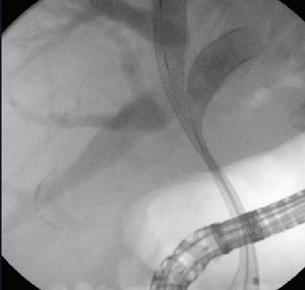

ЕРХПГ, все по-актуален е въпросът за приложението й като първа лечебна стратегия при

МДБО. Няколко систематични и мета-анализа третират въпроса, дали EUS-BD е подходяща за първа линия палиативна дренажна техника при МБО. В мета-анализ от 2020 г. Kakked et al. обобщават резултатите от пет проучвания - 3 рандомизирани и 2 обсервационни, вклюващи 361 пациенти.

И двете процедури демонстрират сходен технически успех (OR: 1.20 [0.44-3.24], I2 = 0%) и клиничен успех (OR: 1.44, confidence interval [CI]: 0.63-3.29, I2 = 0%). Нежеланите реакции (OR: 1.59 [0.89-2.84]) не се различават в двете групи. В ЕРХПГ групата 9.5%

с EUS-BD (risk difference = 0.08%, P = 0.02).

венции също е сходна в двете групи (OR1.68 [0.76-3.73], I2 = 42%). В групата с ЕРХПГ притискане на стента от тумора и туморно прорастване са били чести причини за реинтервенция (ОR 5.35 [1.64-17.50], I2 = 0%). EUS-BD е със сравним технически и клиничен успех с ЕРХПГ и потенциално би могъл да бъде използван като първа линия за палиативен дренаж